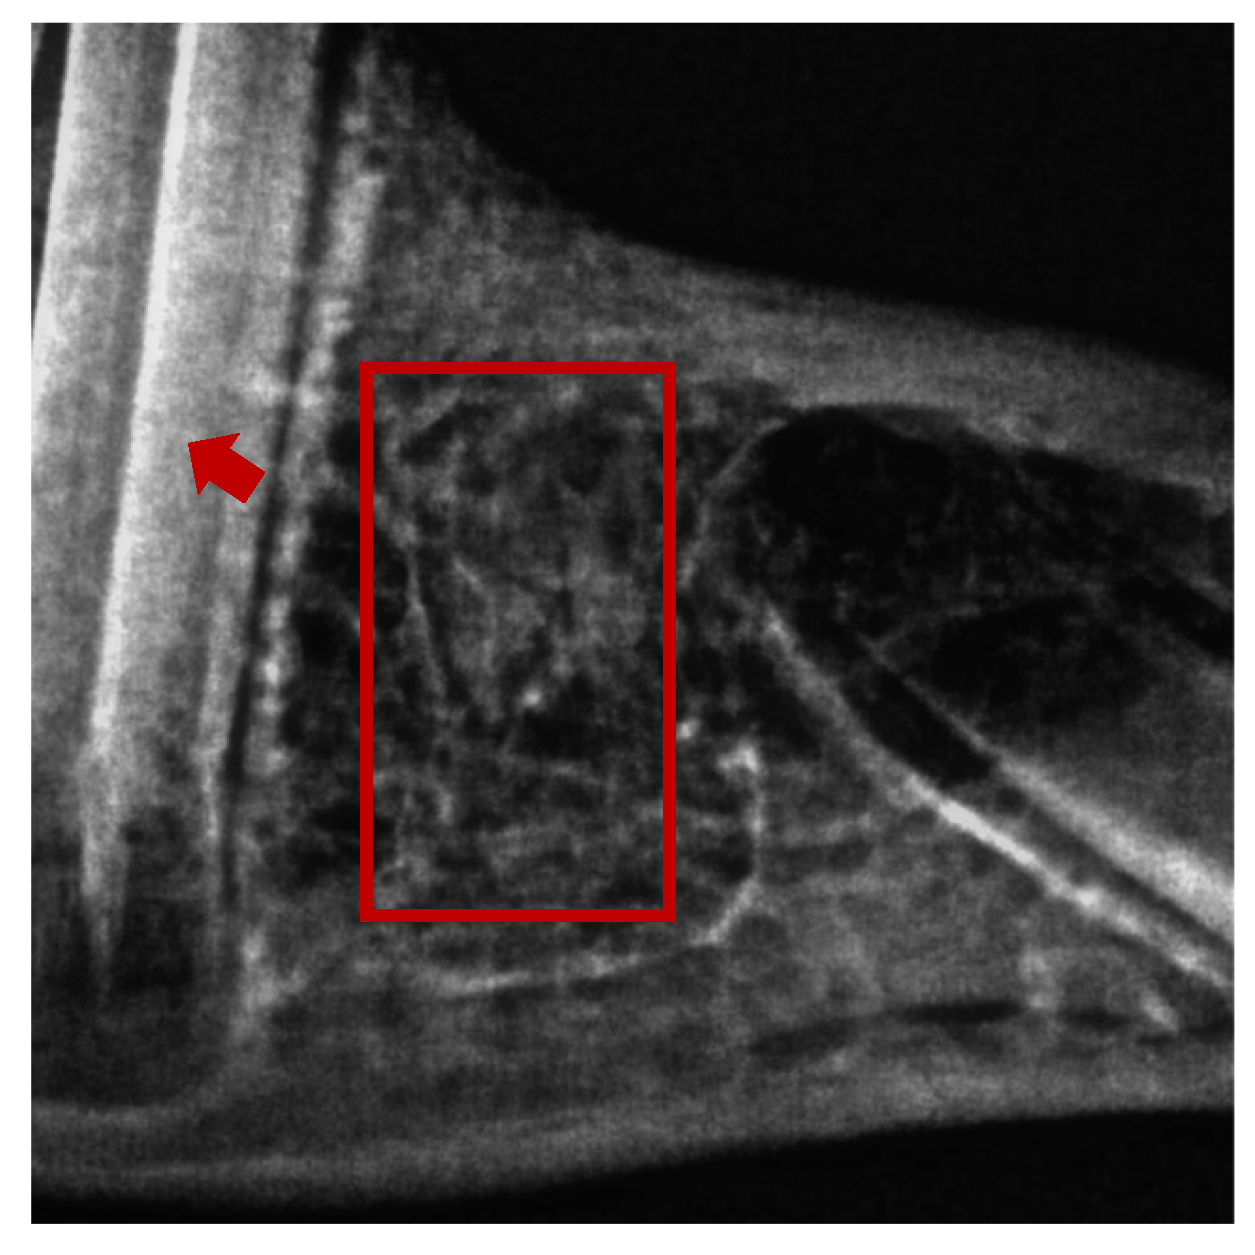

2.2. Histomorphometry

| Histological Parameters | Control Group | Rutin-Treated Group |

|---|---|---|

| Coronal width (mm) | 1.7 ± 0.2 | 1.2 ± 0.3 |

| Middle width (mm) | 0.8 ± 0.32 | 1.3 ± 0.05 |

| Apical width (mm) | 4.5 ± 0.4 | 6.3 ± 0.4 * |

| Bone formation area diameter (mm) | 2.8 ± 0.5 | 4.5 ± 0.4 * |

| Mineralized bone region (%) | 26.6 ± 6.4 | 34.2 ± 4.5 |

| Bone marrow region (%) | 11 ± 3.9 | 32.3 ± 12.1 * |

| Connective tissue region (%) | 46.9 ± 10.9 | 33.0 ± 8.7 |